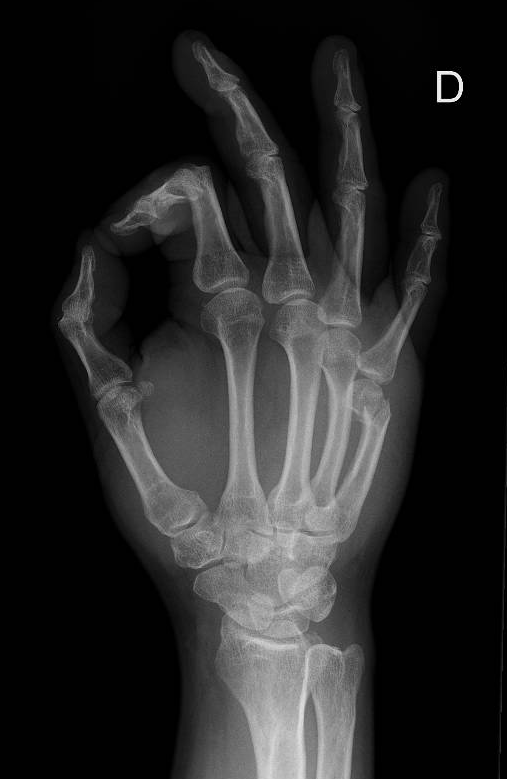

Image 2 : réalisée par M. Karakus